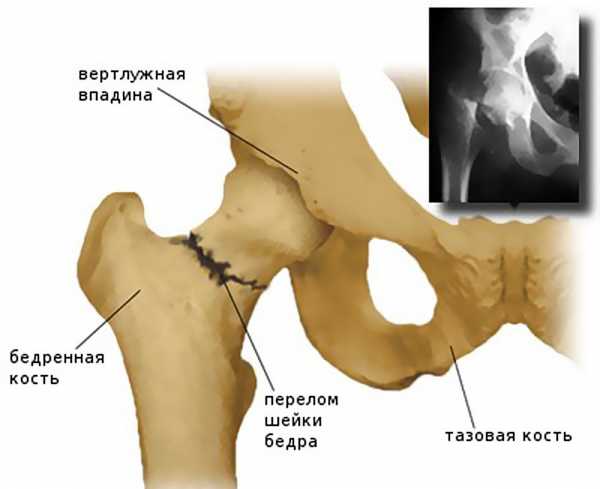

Их структура претерпевает значительные изменения: они становятся мягкими и хрупкими, то есть развивается остеопороз. Он-то и становится главной причиной таких травм, как перелом шейки бедра, запечатленный на этом фото.

Подробнее о шейке бедра

Шейка бедра – это верхний конец бедренной кости, это самая хрупкая часть кости. Шейка является соединяющим компонентом между телом кости и ее головкой. На таз и бедро приходятся наибольшие нагрузки при ходьбе, поэтому нарушения в их работе, а тем более целостности вызывает огромные трудности. Восстановить кость трудно, но даже после этого возможны негативные последствия перелома шейки бедра.

Перелом шейки бедра – это нарушение целостности верхней части бедренной кости в зоне чуть ниже тазобедренного сустава, между головкой бедра и большим вертелом. Является достаточно распространенной травмой, чаще возникает в быту и выявляется у пожилых людей, страдающих остеопорозом. Проявляется умеренной болью, ограничением опоры и движений, а также нерезко выраженным укорочением конечности. Диагноз выставляется на основании симптомов и результатов рентгенографии. При таких травмах очень высок риск несращения, для восстановления функции конечности обычно требуется операция.

Тазобедренный сустав – один из самых крупных суставов. Он выполняет опорную функцию и несет значительную нагрузку при беге и ходьбе. Сустав состоит из шаровидной головки бедра и глубокой округлой вертлужной впадины, окруженных капсулой и мощными связками. Еще одна крупная связка располагается прямо в центре сустава и соединяет дно вертлужной впадины с головкой бедра. В своей периферической части головка переходит в шейку, а шейка – в тело бедренной кости. Шейка расположена под углом к основной части кости, в области угла располагаются большой и малый вертелы.

Пострадавшие с переломом шейки бедра жалуются на нерезко выраженную боль, усиливающуюся при движениях. Кровоподтеки в области повреждения обычно отсутствуют, отек незначительный. При смещении отломков возможно укорочение конечности (не превышает 4 см, больше заметно в положении лежа на спине с выпрямленными ногами). В большинстве случаев выявляется симптом «прилипшей пятки» — пациент не может самостоятельно поднять пятку над поверхностью. Стопа развернута и своим наружным краем опирается о постель. При поколачивании по пятке возникает боль в области тазобедренного сустава и иногда в паху. Пальпация зоны повреждения болезненна.